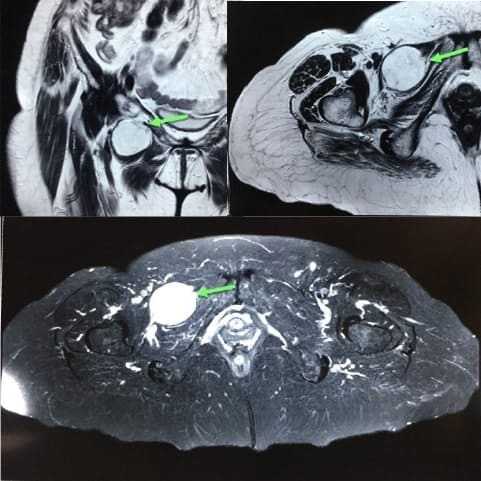

Por último, debido a su superior resolución tisular, la resonancia magnética nuclear (RMN) muestra mayor valor diagnóstico en la identificación de hernias tipo I y sensibilidad similar a la TC en el tipo II y III, sin embargo, su disponibilidad en el ámbito de urgencia tiende a ser limitada o retardada, por lo que no es mejor opción que la TC 17.

Con imágenes coronales y axiales T2 y axial STIR (secuencia empleada que permite suprimir la señal de determinados elementos o tejidos específicos, como grasa o agua), se muestra el saco herniario distendido por líquido entre los músculos pectíneo y obturador externo (Figura 6).

Figura 6. Resonancia magnética nuclear de pelvis que permite visualizar una hernia obturatriz tipo 2. Imágenes coronales y axiales T2 (arriba) y axial STIR (abajo) mostrando saco herniario distendido por líquido entre músculos pectíneo y obturador externo derecho. Fotografías originales tomadas de los estudios de imágenes de pacientes.